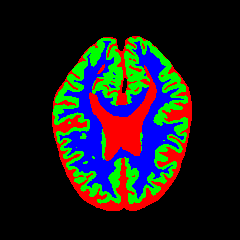

• OASIS-1 [34]: Derived from the Open Access Series of Imaging Studies, this dataset comprises T1-weighted MRI scans from 421 subjects (aged 18–96). The images were acquired with a resolution of 176×208176\times 208 pixels and a slice thickness of 1.25 mm (TR=9.79.7 ms, TE=4.04.0 ms, TI=2020 ms). Following standard protocols, we utilize the provided manual segmentation masks for Cerebrospinal Fluid (CSF), Grey Matter (GM), and White Matter (WM).

7 Qualitative Evaluation

Fig. 8 and Fig. 10 provide qualitative comparisons on the OASIS-1 and MRBrainS13 datasets, respectively. It is visually evident that the baseline predictions (c) and standard augmentations (e.g., (d), (g), (i)) frequently suffer from noisy artifacts, blurred boundaries, and mis-segmentation of intricate anatomical structures. In stark contrast, our ”Ours+” enhanced methods (e.g., (e), (h), (k)) consistently produce segmentation maps that are visibly cleaner, more spatially coherent, and demonstrate significantly sharper adherence to the Ground Truth (b). This superior fidelity is particularly noticeable in the complex sulcal patterns and holds true across all three backbones (rows), confirming that our framework yields more robust and anatomically plausible results.